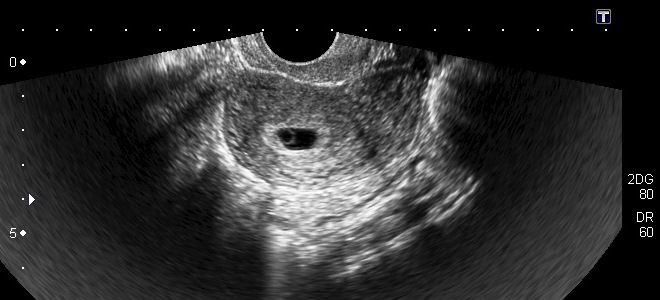

Что показывает УЗИ на 6 неделе беременности?

УЗИ на шестой неделе беременности выполняется нечасто. Обычно для этого существуют определенные показания, такие как угроза прерывания беременности или риск возникновения аномалий. Во время процедуры специалист определяет количество эмбрионов и оценивает функционирование сердечно-сосудистой системы плода, фиксируя частоту сердечных сокращений, которая в норме составляет 140–160 ударов в минуту. Параллельно с этим исключаются возможные патологии.